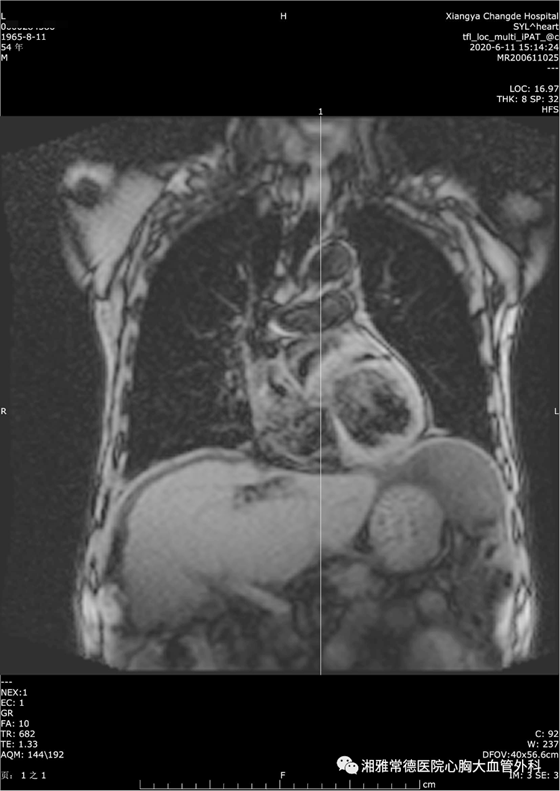

经黄日茂教授查房及科室充分讨论后,认为患者胸闷、全身水肿、多浆膜腔积液应该是心包缩窄导致静脉回流受阻所致。但患者影像检查是不典型的心包缩窄,胸部CT仅见心包部分僵硬、心包少许钙化,心脏彩超发现心包增加不明显,这也是患者多年来一直诊断不明确的根本原因。

完善相关术前检查后,发现无绝对手术禁忌。为慎重起见,心胸外科团队针对刘先生的病症做了充分的胸部疾病MDT及全院讨论,最后同意其心包炎的诊断,并行心脏MRI做进一步确诊。